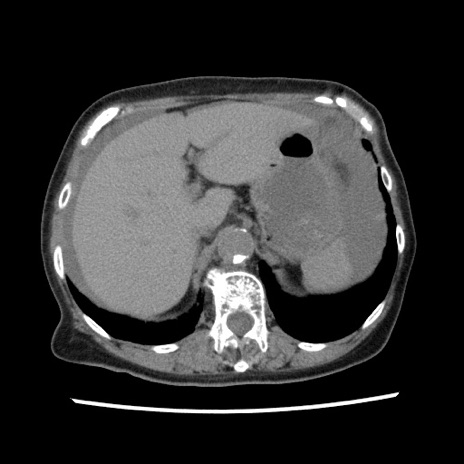

症例1(横断像)

【症例】80歳代女性

【主訴】腹痛

【現病歴】8時間前から腹痛あり来院。

【既往歴】糖尿病、脂質異常症、子宮体癌にて子宮全摘術

【身体所見】意識清明・会話良好だが腹痛で苦悶様、全腹部にわたって反跳痛と圧痛あり

【データ】WBC 13600、CRP 0.14、LDH 224、CK 90